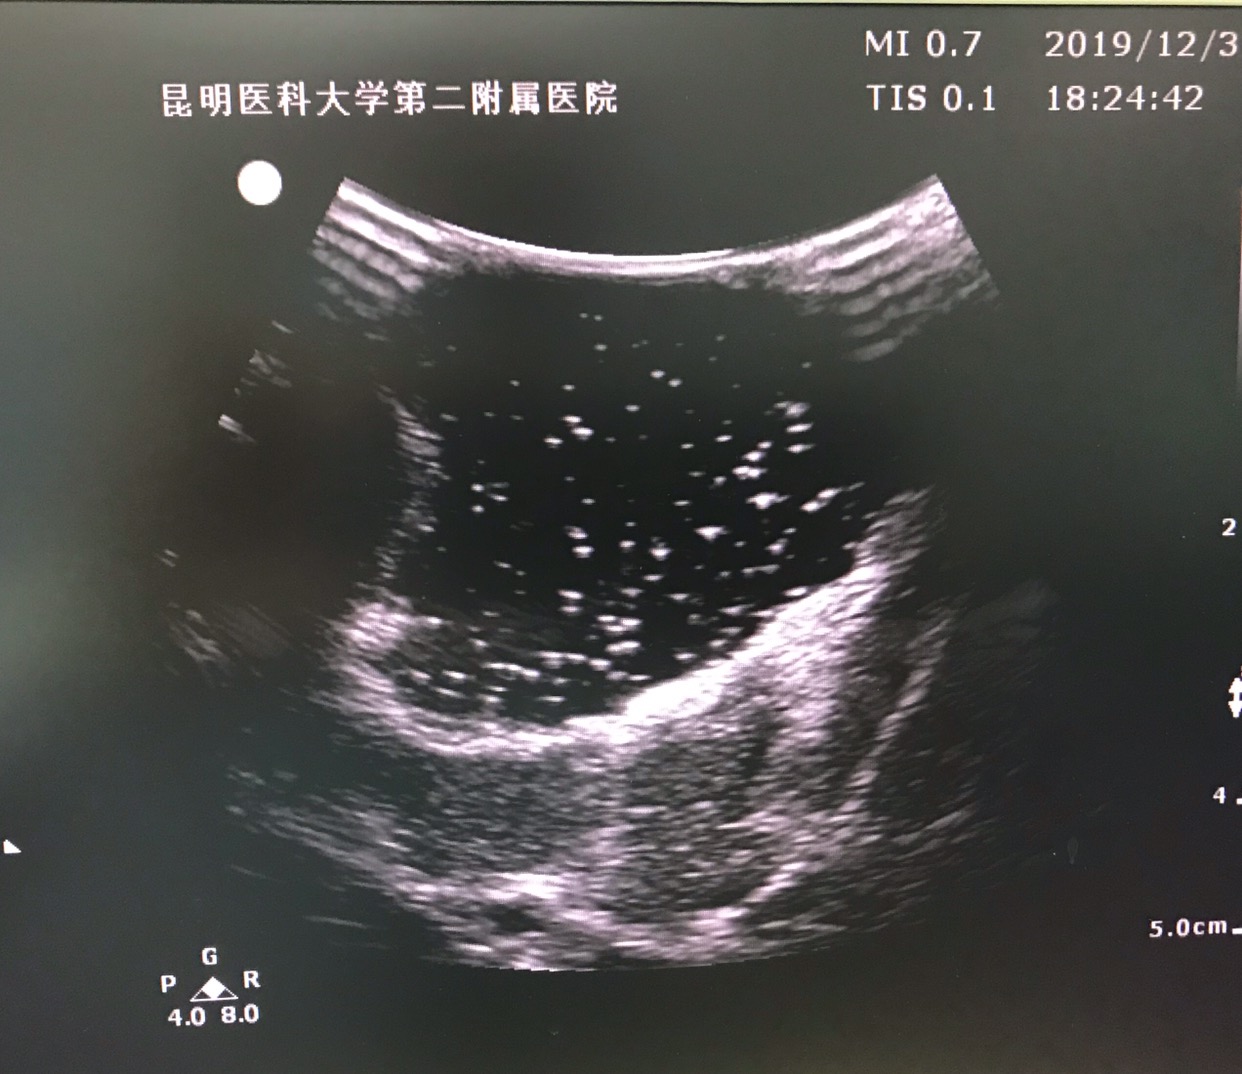

纵切面肿瘤超声影像。

肿瘤切除后再次超声明确无肿瘤残留。